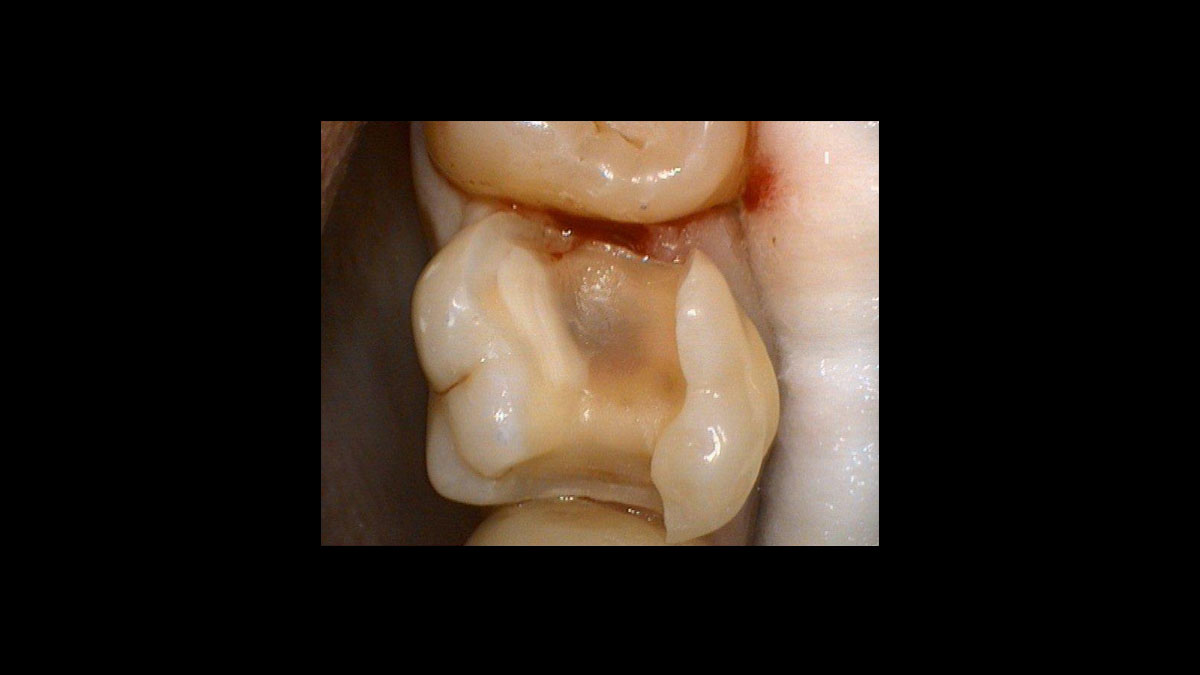

Exposición de un diente desplazado